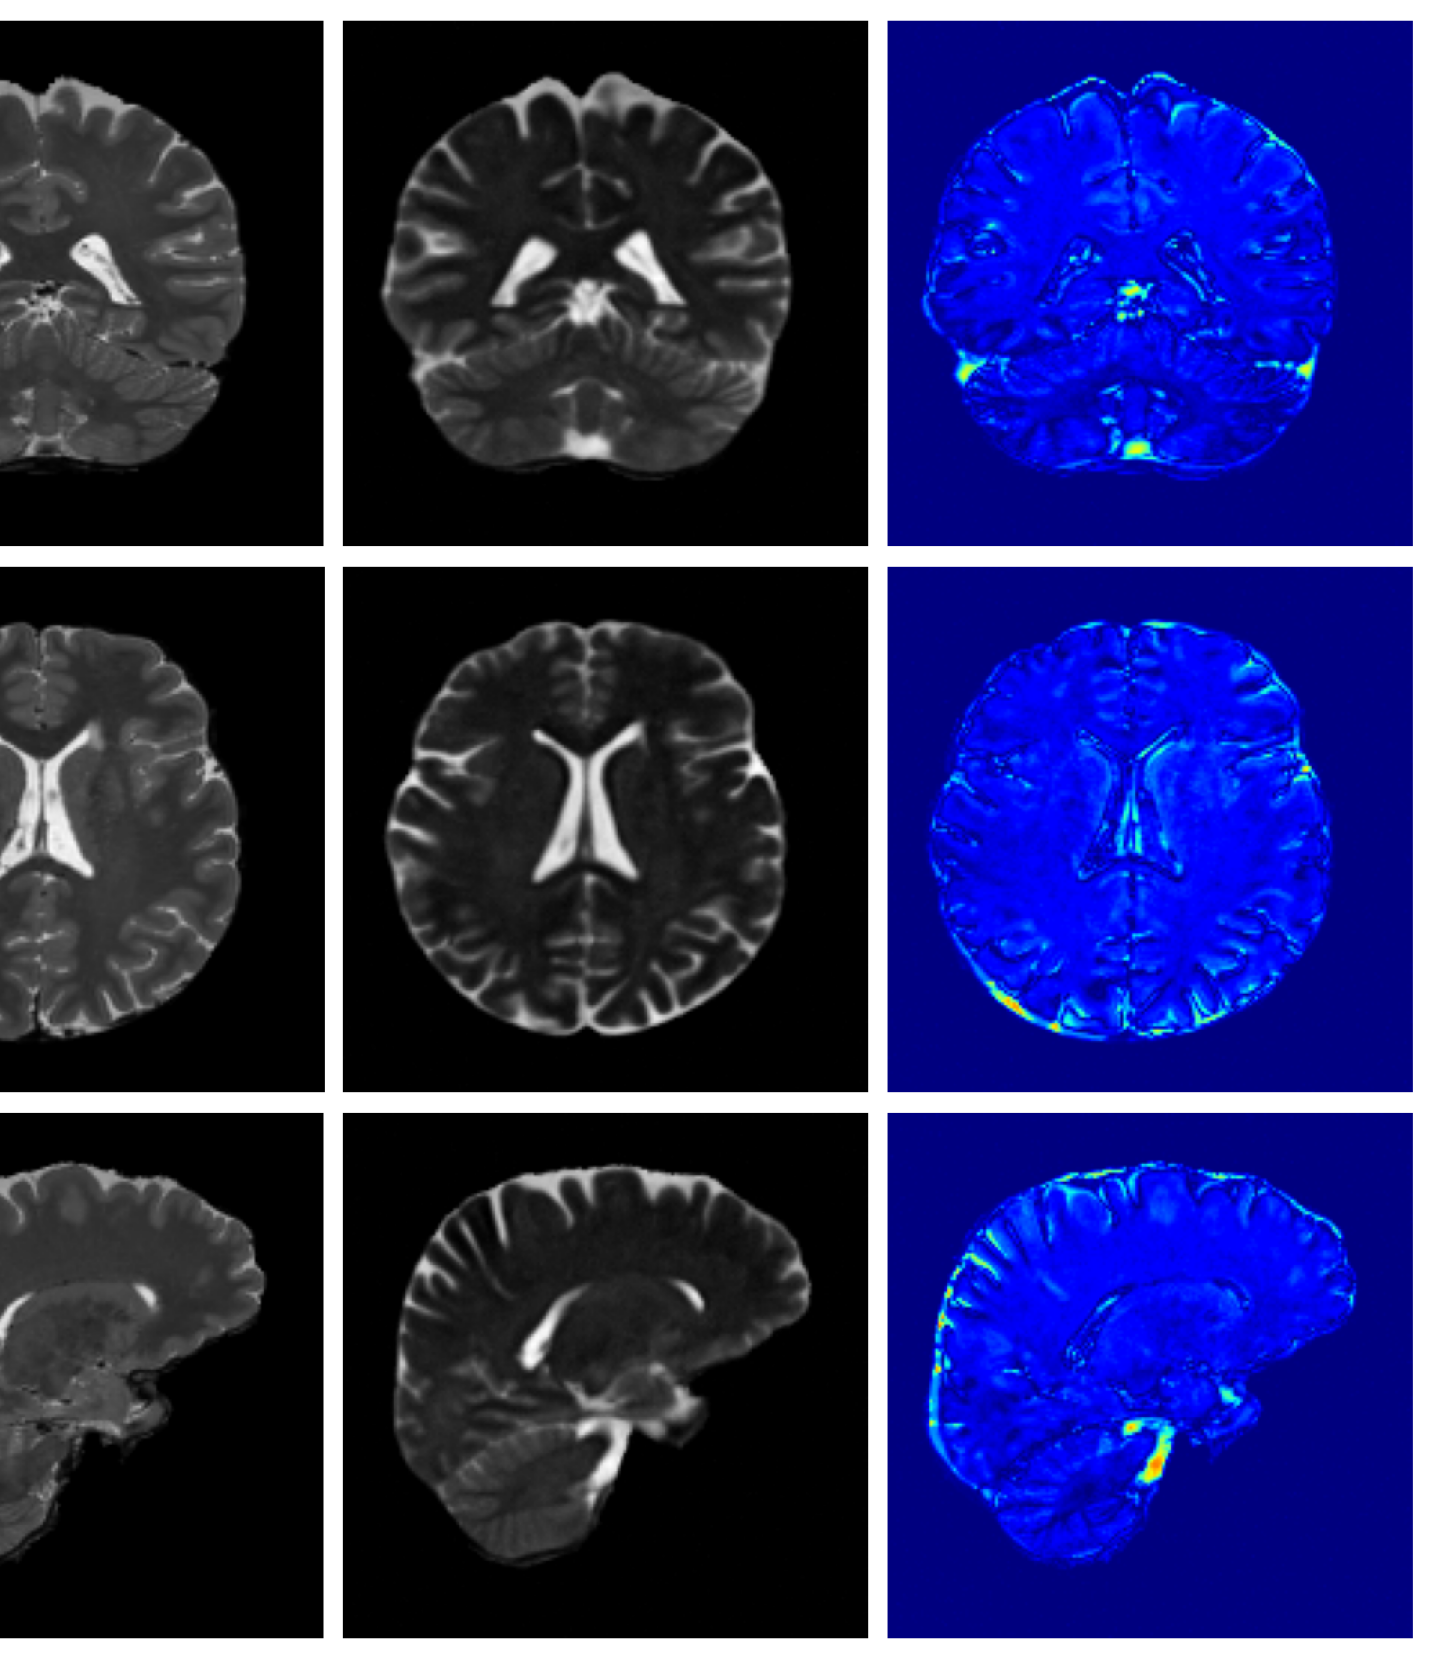

Figure 3 (additional examples in Appendix A.9) shows that SynthSR preserves healthy tissue but struggles with large lesions, while DDPM-2D and DDPM-3D, despite producing high-contrast anomaly maps, generate unrealistic homogeneous inpainting, consistent with their lower performance in Table 3. In contrast, our method yields the most anatomically plausible inpainted regions, although anomaly maps appear subtle due to low contrast between lesions and healthy tissue.